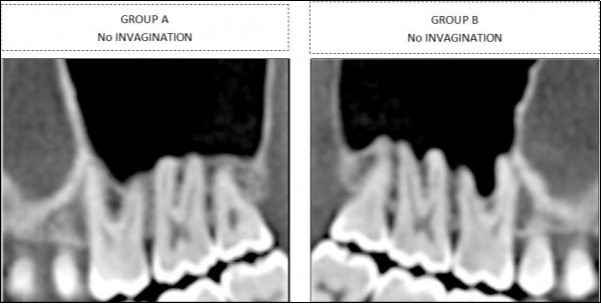

Findings for the molars were classified into two groups, depending upon whether sinus-floor invagination was present between the roots (Group B) or not (Group A) (Figure 2).

Figure 2.Classification in two different categories for molars , based on sinus invagination